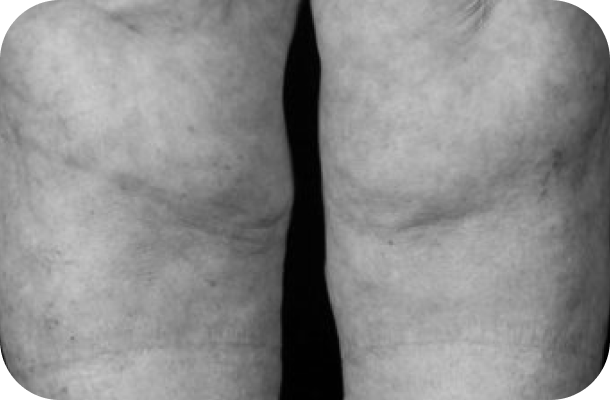

El lipedema no es solo una cuestión estética. Es una condición médica progresiva que causa acumulación anormal de grasa en piernas y brazos, dolor crónico, pesadez extrema y, en muchos casos, vergüenza e incomprensión. Muchas mujeres pasan años sin diagnóstico, sintiéndose frustradas y sin respuestas.